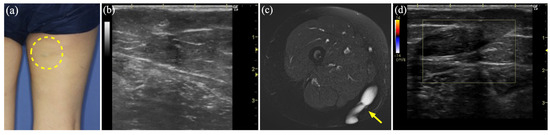

3.6. Case 7

| 7 | 35 | F | Rt thigh | LM | US, MR, CT | Sc, 2 times | Epidermal cyst | 440 |